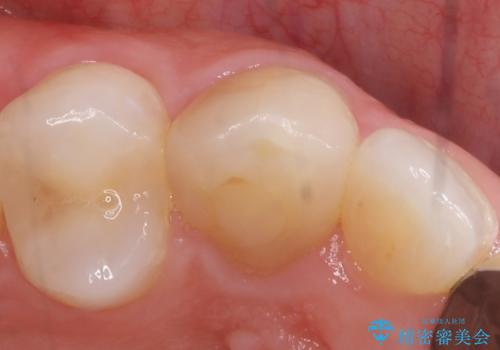

- 数年前に右上3の根管治療を行ったが、段々と色が気になってきたので、セラミックによる治療を行いたいといらっしゃった方の症例です。

再根管治療終了後、オールセラミッククラウンによる補綴を行いました。